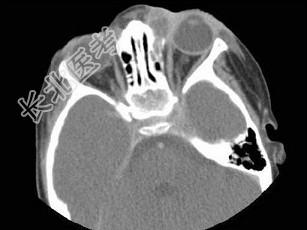

- 多项选择题女,2岁, 左侧眼睑肿胀发热,CT检查如图所示, 正确的描述或诊断是 ( )

A、左侧鼻骨外侧旁见软组织块影

B、其内密度不均,可见低密度影

C、左侧鼻泪管囊肿

D、鼻泪管脓肿

E、混合瘤